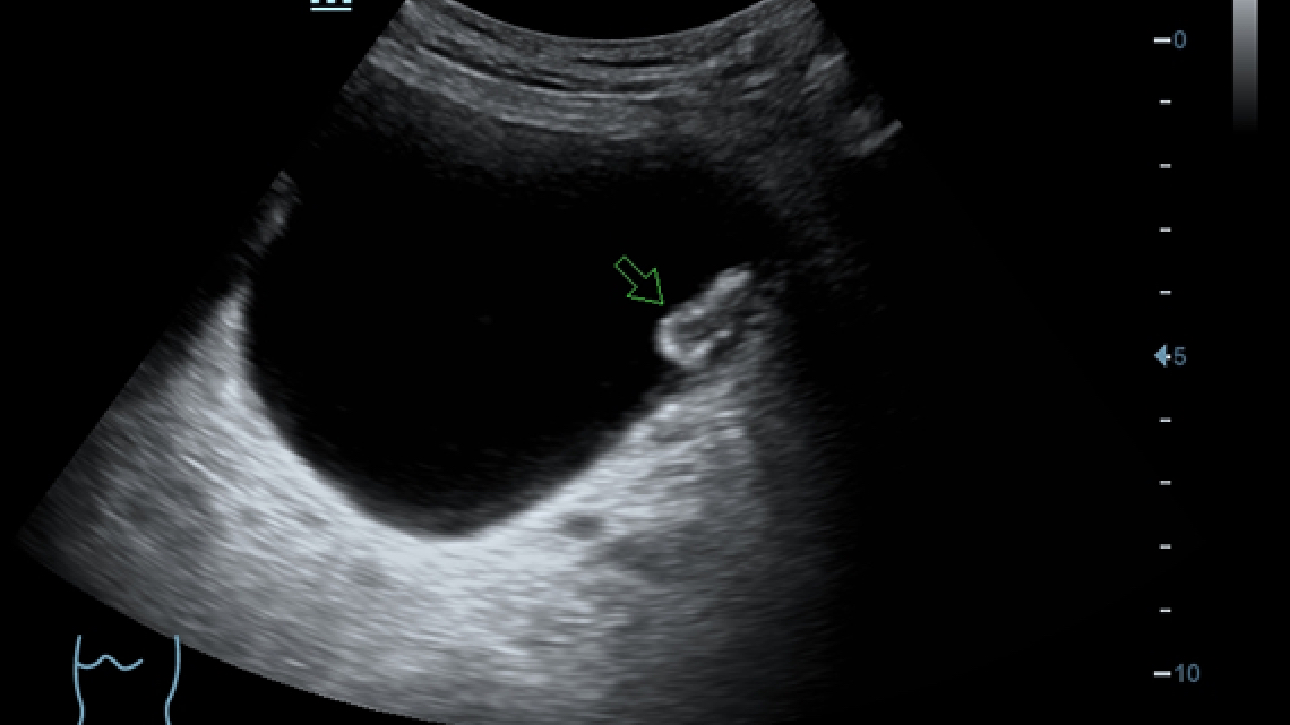

X-Insight, daha geli?mi? g?rĂŒntĂŒler elde etmek i?in kapsaml? bir ??zĂŒmdĂŒr.

Mindrayâin yeni ??zĂŒmĂŒ, geli?en en yeni ultrason teknolojileri ile birlikte, mĂŒ?terilerin g?rĂŒ?lerini klinik gerekliliklerle tam anlam?yla birle?tiren bir ??zĂŒmdĂŒr. Taptaze bir ruhla, gelece?e odaklanarak ve s?n?rs?zl???n pe?inde ko?arak, artan ?l?eklenebilirlikte sĂŒrekli olarak geli?en bir ??zĂŒmdĂŒr.

?ok y?nlĂŒ bir partner olarak, X-Insight'l? DC-60 Exp, her y?nĂŒyle gĂŒnlĂŒk klinik uygulamay? kolayl?kla ve belirsizlik olmadan y?netmenize yard?mc? olacak kapsaml? bir ??zĂŒm sunar.

MĂŒ?teri gereksinimlerine y?nelik g?rĂŒ?ler temelinde, X-Insight'l? DC-60 Exp, eXpress Clarity, eXceptional Intelligence ve eXceeding Experience ile gĂŒ?lendirilerek, hassas g?rĂŒntĂŒlemeyle yĂŒksek verimlilik sa?layacak ?ekilde tasarlanm??t?r.